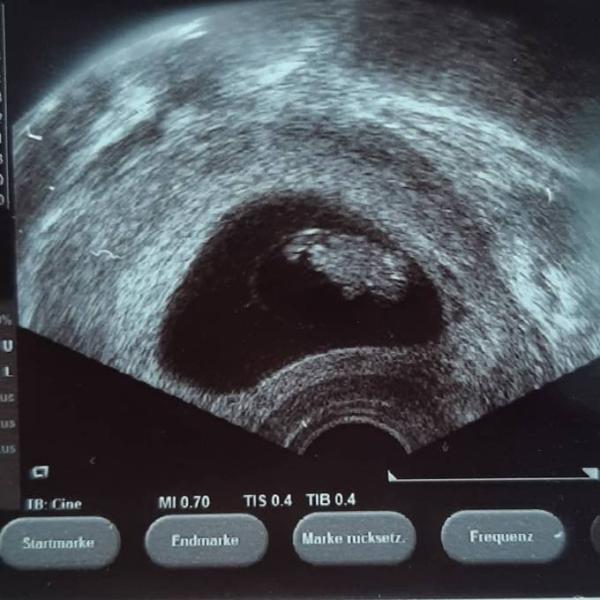

Herzlichen Glückwunsch. Ich war gestern auch bei der FÄ 9+3. Meins wäre schon bei 10+0. Sie hat auch nix um datiert. ET wird bei 3.4. belassen. Mein Krümel hat auch ganz fein geturnt, dabei hatte ich solche Angst das wieder was schief geht. Jetzt bin ich aber unheimlich dankbar das alles gut ist.

Bild zu